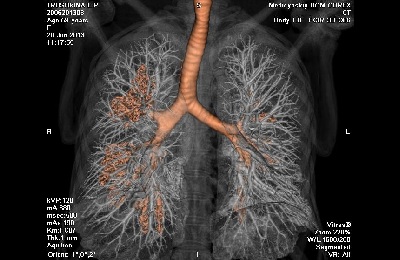

Проведение компьютерной томографии дает возможность выполнить серию послойных снимков грудной клетки с заданной толщиной срезов. Обрабатывая полученные снимки, выполненные в разных плоскостях, компьютер может создать трехмерное изображение легких и органов средостения.

Для улучшения визуализации новообразований в легких применяется метод контрастирования (КТ-ангиография). В вену пациента вводят контраст, который быстро с током крови достигает малого круга кровообращения и «,подсвечивает», сосуды легких.

Суть контрастирования при опухолях в том, что новообразования имеют более разветвленную кровеносную систему, чем окружающие ткани, поэтому именно в раковых сосудах контраст будет накапливаться больше всего.

Компьютерная томография легких может выполняться в нескольких режимах:

- пульмональном, когда основными четко определяемыми структурными элементами грудной клетки являются бронхи, междолевые щели, межсегментарные перегородки, сосуды легких,

- средостенном, когда детально визуализируются органы средостения (сердце, верхняя полая вена, аорта, трахея, лимфоузлы).

Для обнаружения новообразований в легких чаще используют пульмональный режим, а при наличии метастазирования этой опухоли – оба.